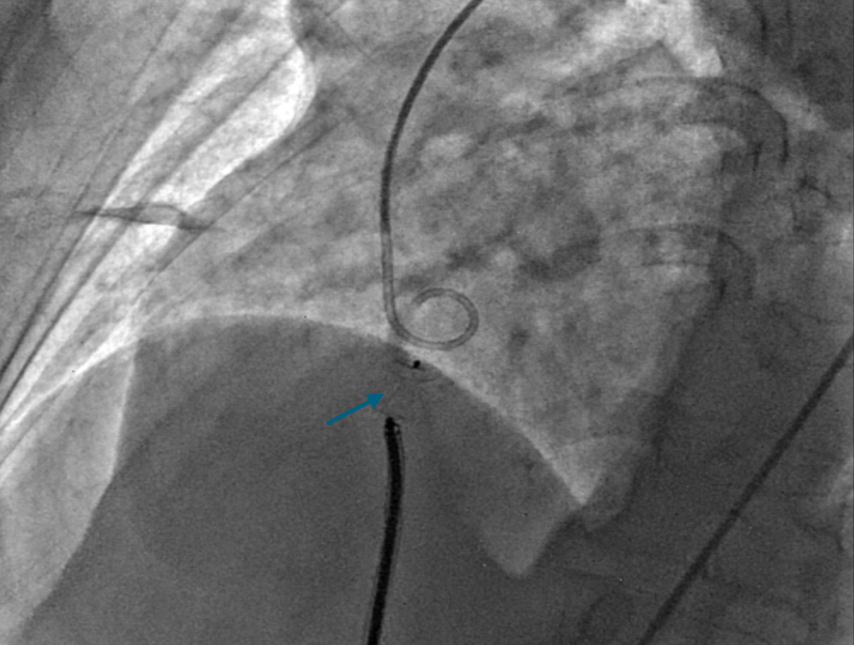

A 7 French delivery sheath was traversed across the ruptured sinus, through the inferior vena cava, to the aorta (Figure 3, Video 3).

Figure 3. Advancement of a 7 French (F) sheath (green arrow) across the arteriovenous (AV) rail.

Gentle traction was exerted on the delivery cable to confirm seating of the left disc on the aortic side without slippage into the ruptured SVA. The rest of the occluder was deployed on the right side across the lesion (Figure 5A-B, Videos 5A-B).

Figure 5. (A) Device deployed (purple arrow). (B) Transthoracic echocardiography.